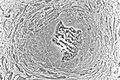

![]() Osteoblasts (blue) rimming a bony spicule (pink - on diagonal of image). In this routinely fixed and decalcified (bone mineral removed) tissue, the osteoblasts have retracted and are separated from each other and from their underlying matrix. In living bone, the cells are linked by tight junctions and gap junctions, and integrated with underlying osteocytes and matrix H&E stain. | |

Hematoxylin and eosin staining (H&E) shows that the cytoplasm of active osteoblasts is slightly basophilic due to the substantial presence of rough endoplasmic reticulum. The active osteoblast produces substantial collagen type I. About 10% of the bone matrix is collagen with the balance mineral.[2] The osteoblast's nucleus is spherical and large. An active osteoblast is characterized morphologically by a prominent Golgi apparatus that appears histologically as a clear zone adjacent to the nucleus. The products of the cell are mostly for transport into the osteoid, the non-mineralized matrix. Active osteoblasts can be labeled by antibodies to Type-I collagen, or using naphthol phosphate and the diazonium dye fast blue to demonstrate alkaline phosphatase enzyme activity directly.

Light micrograph of decalcified (a process that removes the mineral) cancellous bone displaying osteoblasts actively synthesizing osteoid, containing two osteocytes.